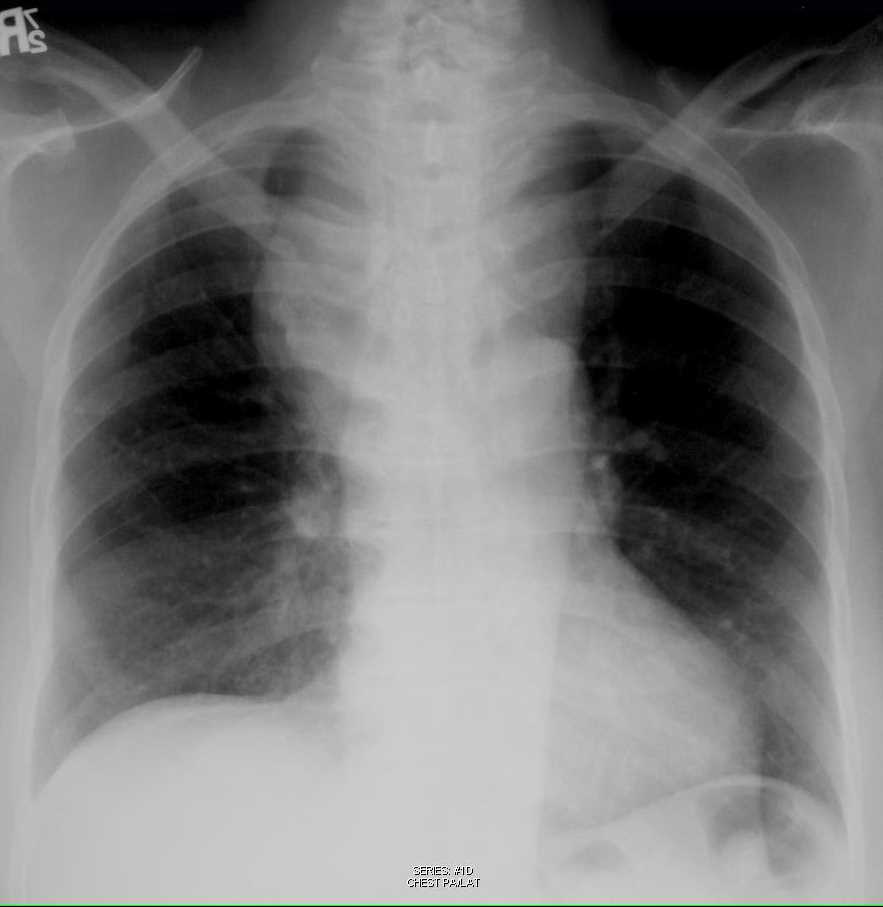

Chest xray showing a large well defined opacity in the left hilar

Chest xray showing a large well defined opacity in the left hilar Chest X Ray For Goitre A thyroid gland that is enlarged for any reason is called a goiter. Symptoms are typically mechanical/compressive in. A goiter can be seen when the thyroid is overactive, underactive or. Goiter (rarely thyromegaly) refers to enlargement of the thyroid gland. Sometimes computerized tomography (ct) scan or magnetic resonance. It can occur from multiple conditions. A surgeon with an understanding of. Chest X Ray For Goitre.